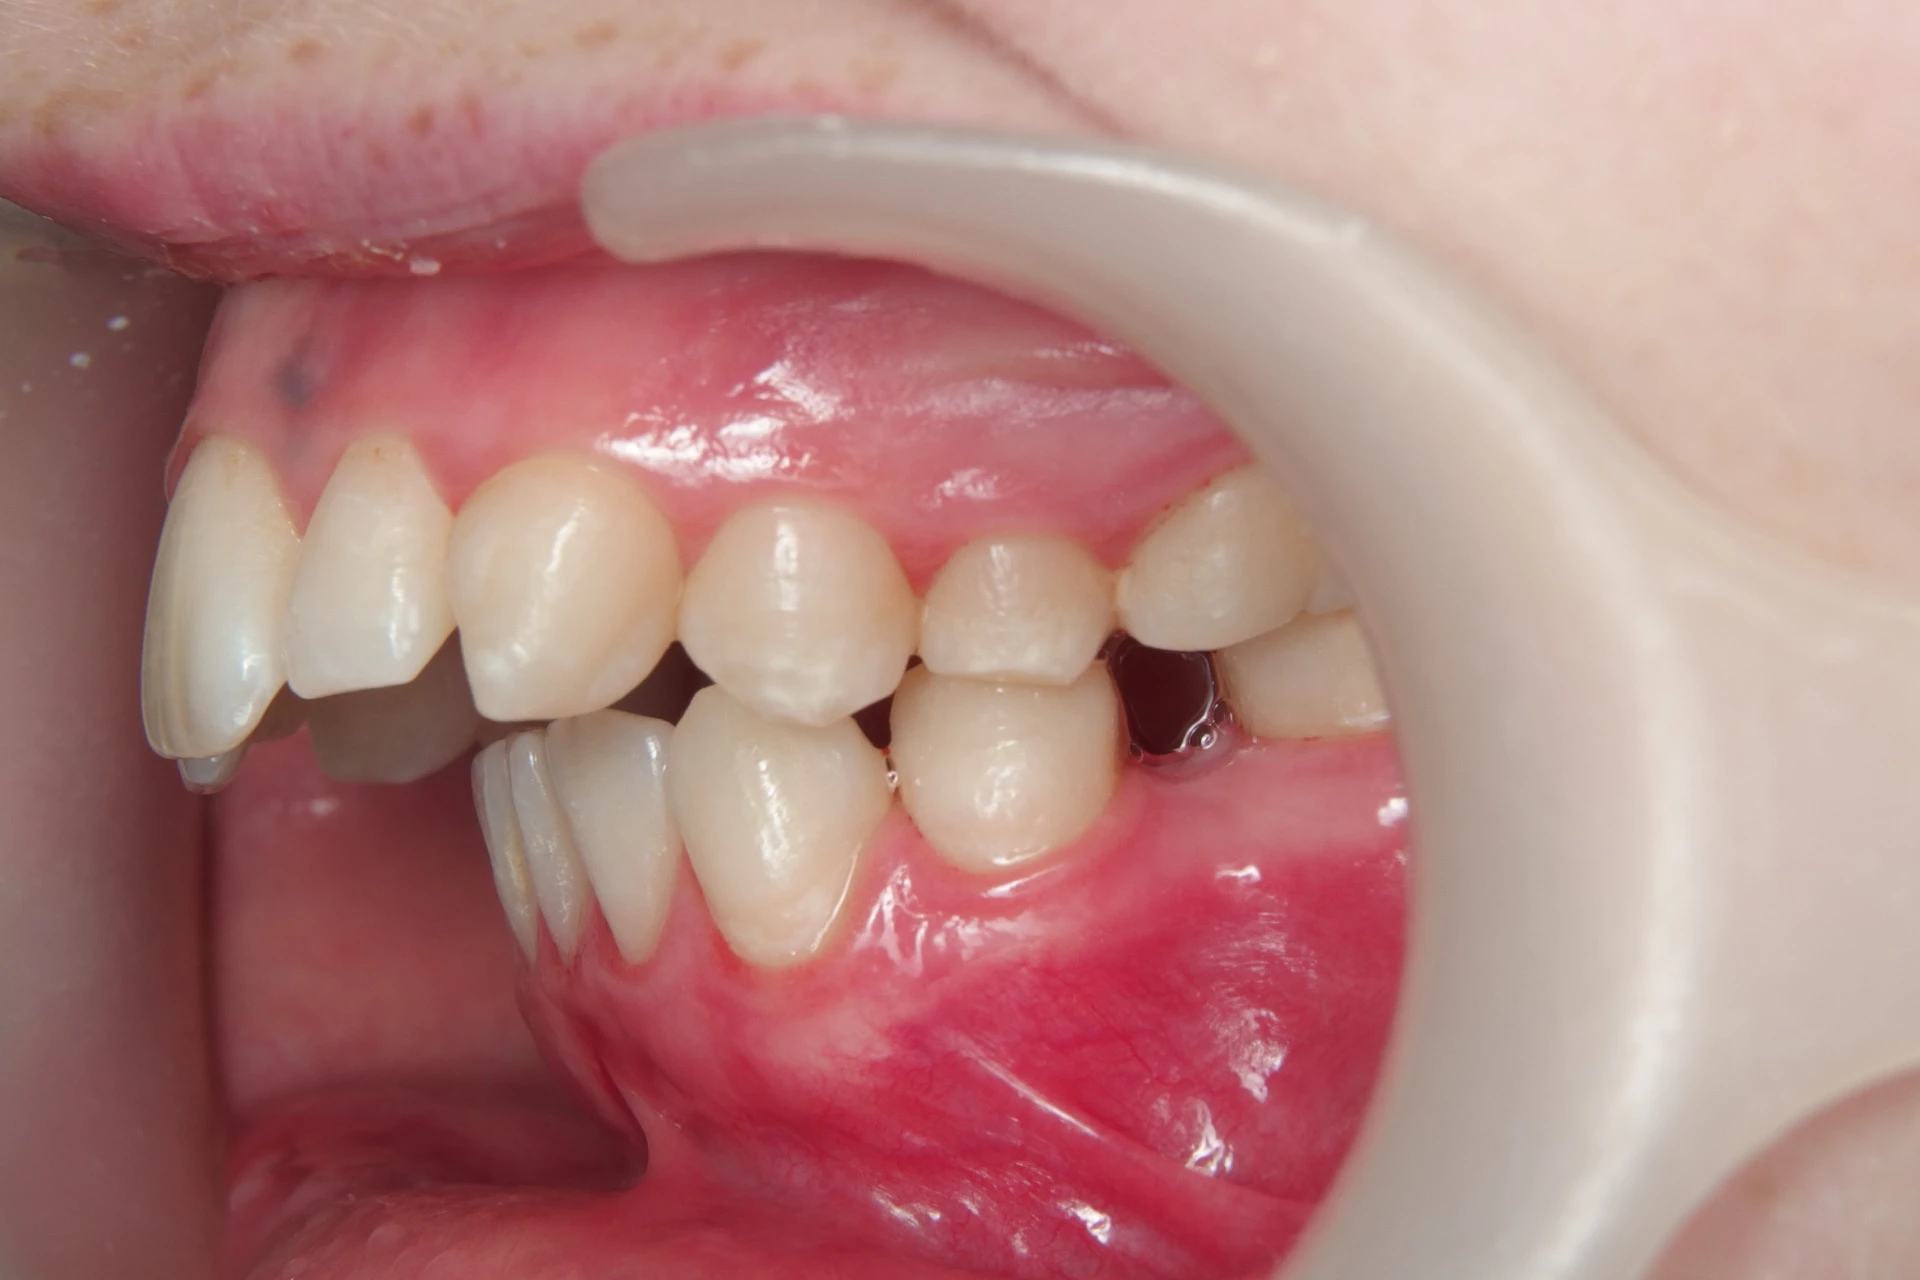

Vårt arbeid

Alle pasienter som vises har gitt skriftlig samtykke til at bildene kan brukes på klinikkens nettside.